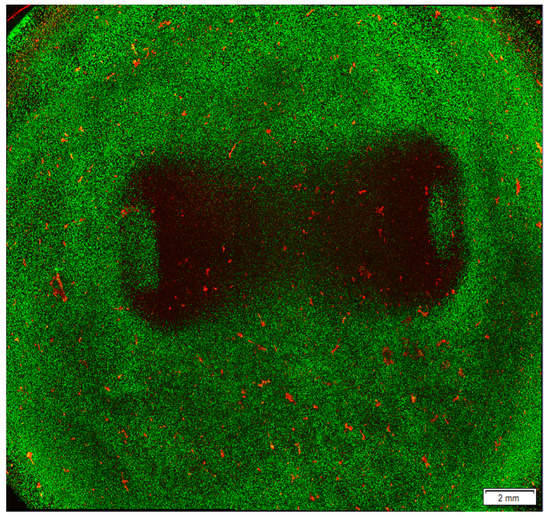

- Csepe, T.A.; Hansen, B.J.; Fedorov, V.V. Atrial fibrillation driver mechanisms: Insight from the isolated human heart. Trends Cardiovasc. Med. 2017, 27, 1–11. [Google Scholar] [CrossRef][Green Version]